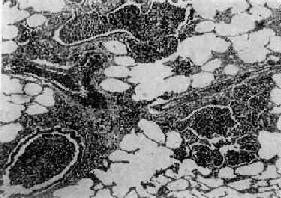

图9-15 大叶性肺炎

肺泡腔内充满纤维素性渗出物,纤维素丝穿过肺泡间孔,使相邻肺泡内的纤维素网互相连接